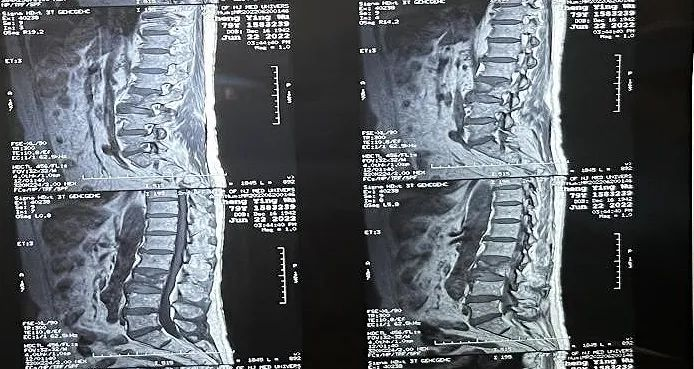

患者情況:腰椎L3壓縮性骨折

南京醫科大學第二附屬醫院骨科副主任醫師王伯堯帶領團隊成功完成經皮椎體球囊擴張成形術(PKP)。該患者為腰椎陳舊性壓縮性骨折,腰部疼痛難忍,活動受限,生活受到影響。王醫生借助普愛醫療大平板C臂機高清的圖像及靈活的擺位,快速定位椎弓根位置,確定進針點,使得手術得以更加高效和準確地完成。

患者術前影像